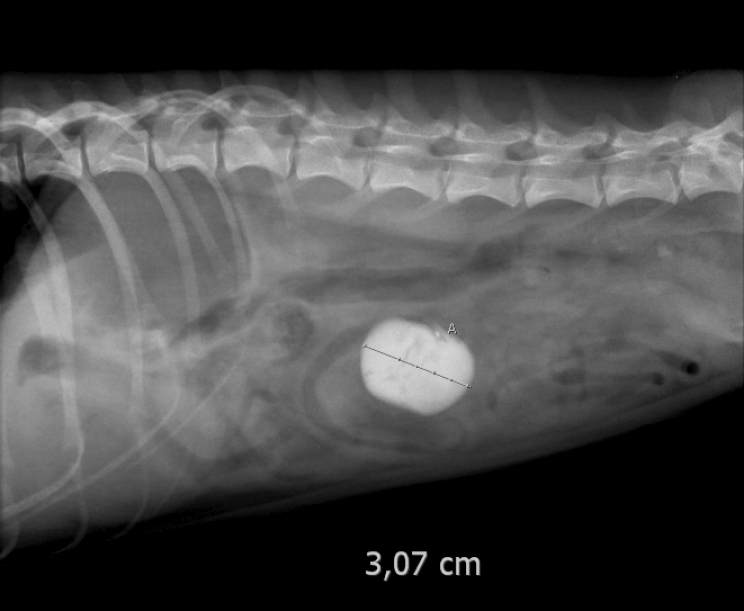

Nel caso di oggetti metallici, sassi o ossa, oggetti densi che si vedono bene nelle radiografie, le cose saranno più semplici perché sappiamo già dove cercare; per le cose meno dense come plastica o spago le cose sono più complesse, perché non sempre si riesce a capire che ci sono (non si vedono nelle lastre); è il padrone a dover seguire il cane quando è a casa e cercare di capire se ci sia un oggetto mancante, in modo da poter dare tutte le possibili informazioni utili al veterinario ed evitando, nel caso la causa non risultasse un corpo estraneo, di aprire inutilmente l'addome dell'animale.